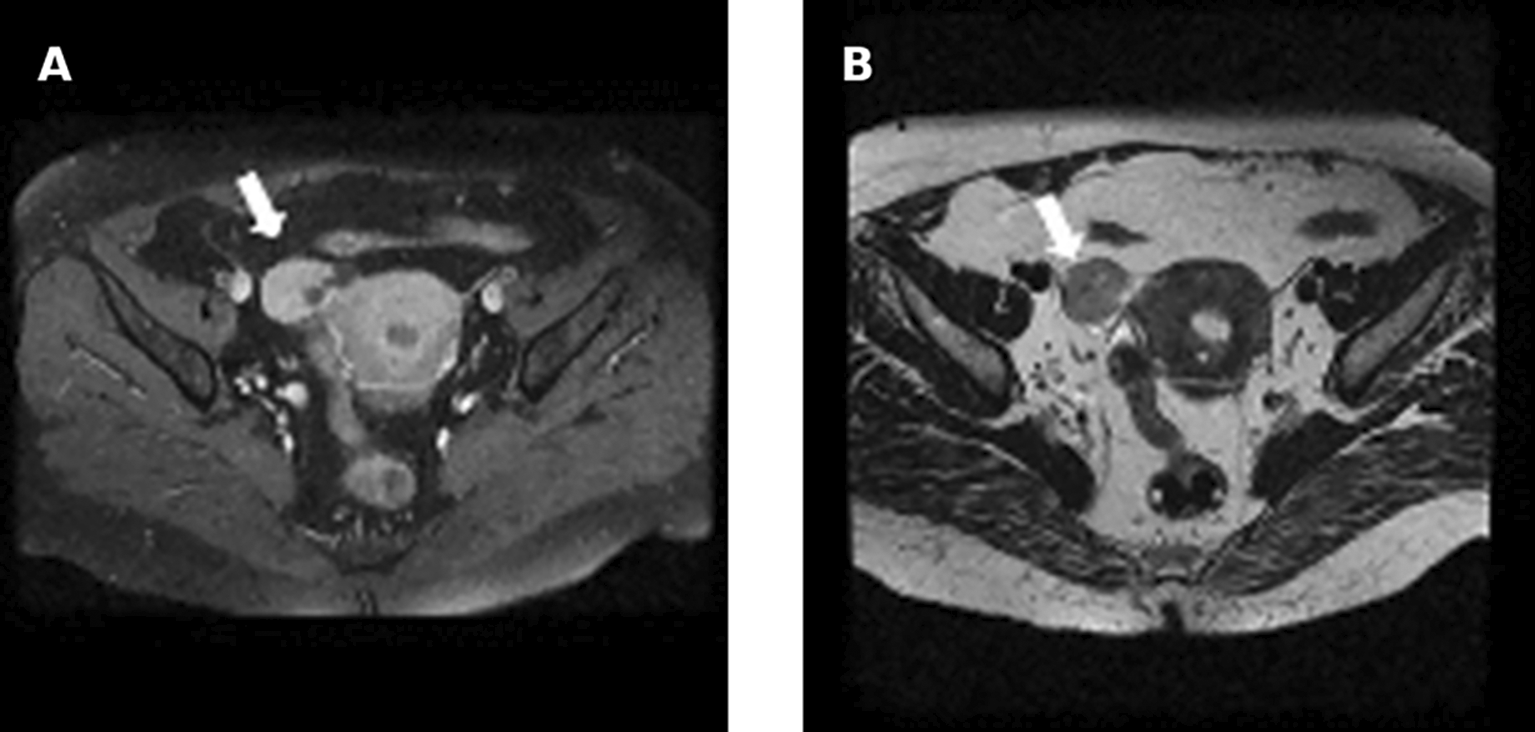

Pelvic ultrasound showed an enlarged uterus and right ovary (measured at 60*30 mm). MRI revealed an enlarged right ovary, with several follicles as well as a solid mass with intermediate signal on T2 and avid enhancement after gadolinium administration. The left ovary was of normal size 26*24 mm. No mass was found ( Figure 7).

Testosteronemia was at 9.22 nmol/l with normal levels of SDHEA (873 ng/ml). Lab tests revealed a normal basic cortisol level with no findings suggestive of cushing’s syndrome. A Thoraco-abdominopelvic CT was performed showing a 30mm right adrenal mass with spontaneous density at 7 HU and an absolute wash out at 35% suggestive of an adenoma. Pelvic MRI revealed a solid left ovarian mass with heterogeneous signal on T2 with an intermediate risk time intensity curve (B) on dynamic contrast enhancement, classified as ORADS category 4 ( Figure 12).